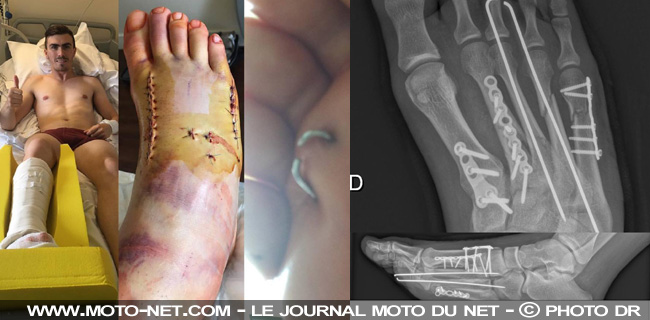

"L'opération s'est bien passée", rassure Loris sur les réseaux sociaux, photos "choc, gore, trash, fail, WTF, (pas) sexy" (!) à l'appui... "Trois plaques, plusieurs vis et deux clous", énumère le patient "impatient" de retrouver la compétition mais satisfait du boulot accompli par son chirurgien, le Dr Adrien Ray, à l'hôpital de La Tour à Meyrin (Suisse).

"L'un des métatarses était vraiment mal fracturé, mais le Dr Ray a fait un super travail !", précise l'unique pilote français en MotoGP. "Malheureusement et comme vous vous en doutez, je ne serai pas présent à Barcelone", avertit le n°76 du team Ducati Avintia qui sera remplacé par le pilote d'essai Michel Pirro.